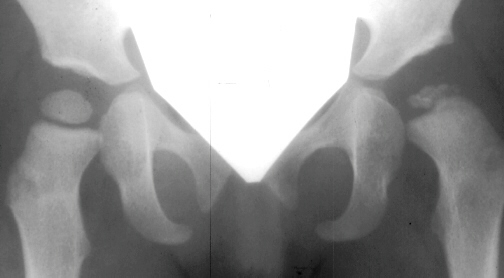

Four months later, the spica cast was removed and an Atlanta brace was applied. X-rays showed avascular necrosis at ten months of age . At two years of age, the ossification of the left nucleus was still delayed. The leg lengths were equal and the range of motion of the hip was full.

The progression of the hip is documented by x-rays taken at 1 year of age, 2 years of age, 3 years of

age, 5 years of age, 7 years of age, then at ten years of age, early closure of the lateral portion of proximal growth plate observed. Coxa valga was also observed.